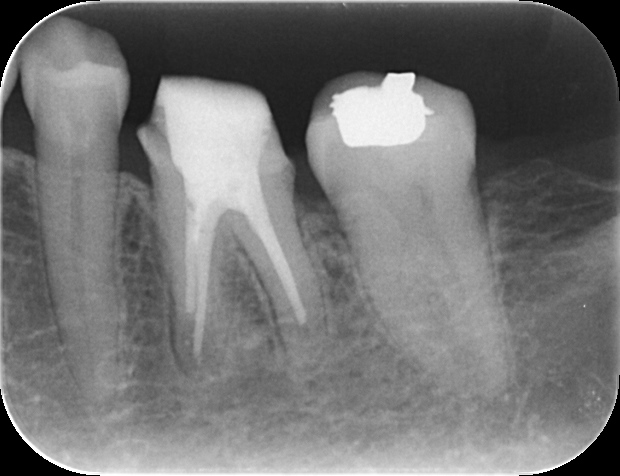

症例 再根管治療後の外科的歯内療法 2025.11.12 【背景】 ・60代女性。 他院で処置するも治らず、専門医による根管治療を希望し来院 外科的歯内療法の可能性を説明し、通法通り処置後、セラミックにて修復 その後、2年ほど経過し、根尖に病変を認めた為、外科的歯内療法へ移行し、 1年経過後のレントゲン写真にて治癒確認 歯内療法完了後 外科的歯内療法直後 1年経過時のレントゲン 【総評】 処置前の診査診断にて、治療の成功率や、外科的歯内療法の必要性について、必ず説明していますが、 一定期間が過ぎてしまうと忘れてしまう患者様は一定数いらっしゃいます セラミック修復した歯を壊す必要がなく、また、抜歯からインプラントへ移行する可能性を減らすことができるため、 難易度は高い処置ですが、専門医で対応することの意義は大きいと感じる症例をご紹介しました 根管治療でお困りの方や、クリニックの関係者の方は、ご紹介フォームからお気軽にお問い合わせください この記事のタイトルとURLをコピーする